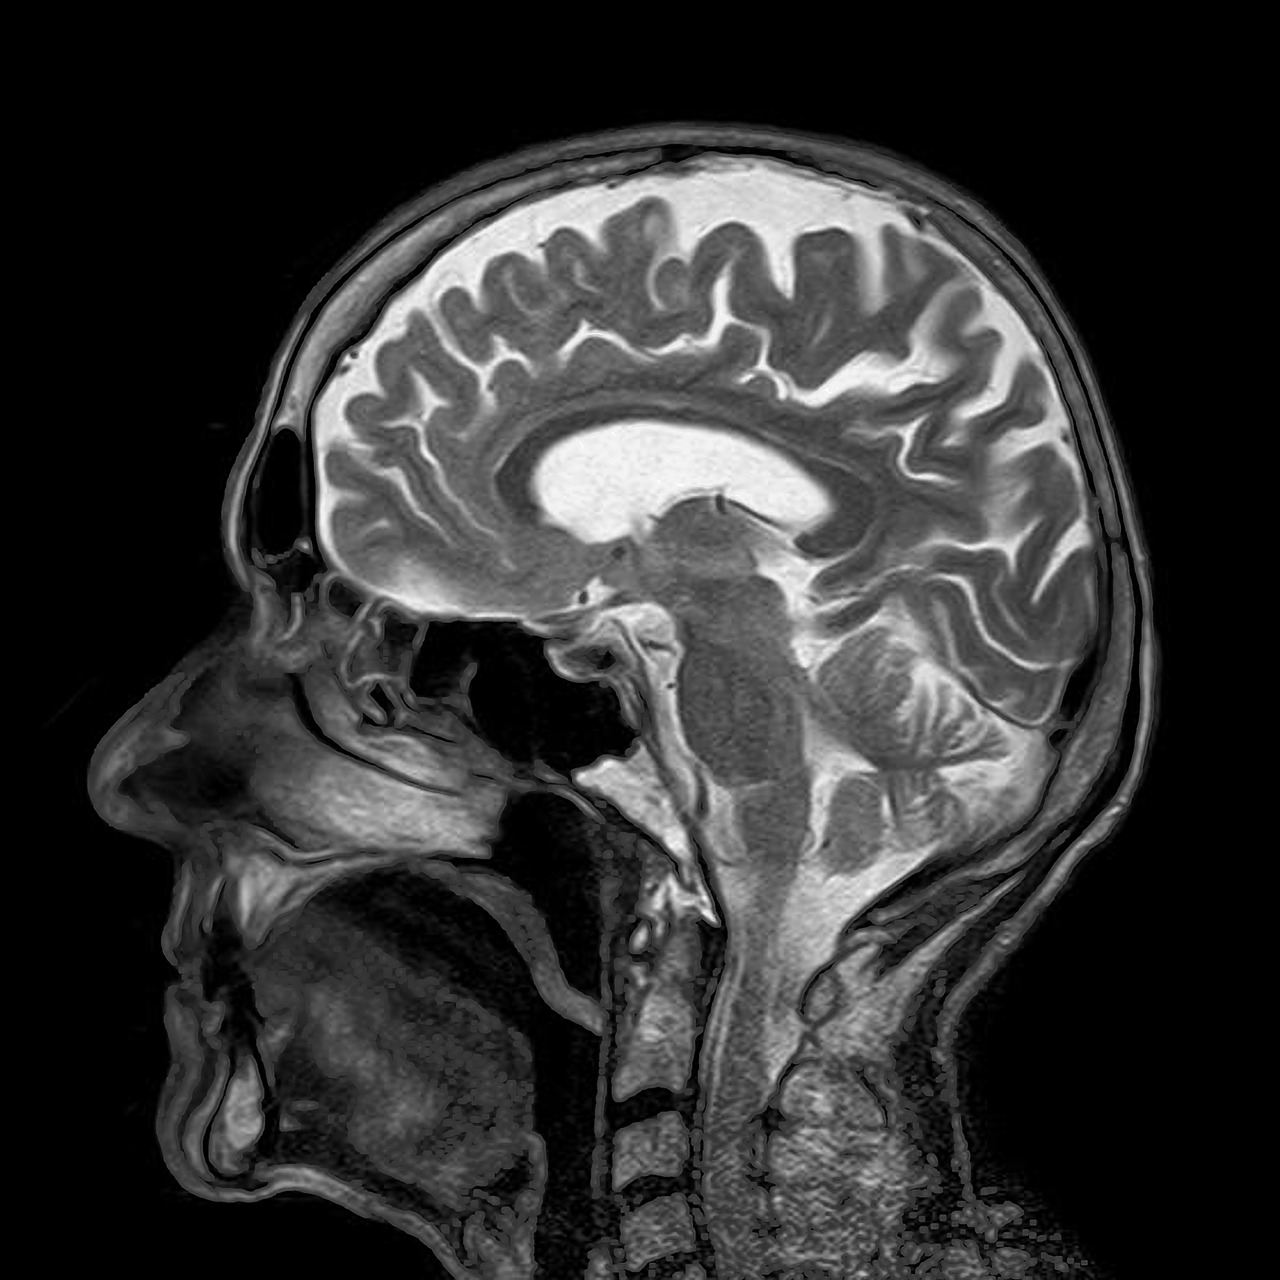

2. 자기공명영상(Magnetic resonance imaging : MRI)

자기공명영상(MRI)은 자기장 사용으로 해상도가 컴퓨터단층촬영(CT)보다 높아 뇌의 미세구조를 확인할 수 있다. 알츠하이머병의 국소적인 뇌 위축, 뇌혈관 질환 등에서 활용할 수 있다. 그러나 촬영 시간이 30분 정도로 길고 비용이 CT보다 비싸다. MRI 촬영 비용은 병원 규모, 건강보험 급여 적용 등에 따라 다르며 약 20만 원~80만 원 정도이다. 자기장을 사용하기에 몸속에 금속 물질이 있을 경우 촬영 가능 여부를 확인하여야 한다. 통 안에서 움직임 없이 20~40분 촬영해야 하므로 폐소공포증이 있을 경우 촬영이 어려울 수 있다. 치매 진행속도가 빠른 경우 감염, 독성질환 등 여러 질환을 감별하기 위해 조영제를 사용할 수 있다. MRI는 T1강조영상, T2강조영상, T2기울기에코영상, 확산강조영상, 기능자기공명영상 등 다양한 기법이 있다.